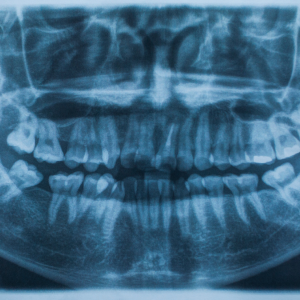

Anaya's journey to Malhar Dental Clinic began when her toothache became unbearable, prompting her to act. Upon her visit, Dr. Rohan, the clinic's esteemed dentist, suggested a dental X-ray to get a clearer picture of her oral health. Dr. Rohan explained that the X-ray would help detect any cavities, infections, or bone loss that might be causing her pain, offering a sense of relief to Anaya.

As Anaya lay on the comfortable chair in the clinic's serene environment, she felt a sense of reassurance. The gentle hum of the X-ray machine was a testament to the technology that would soon provide answers to her dental woes. Within minutes, Dr. Rohan had the X-ray results, revealing a cavity that had reached the nerve of her tooth—a problem that, if addressed earlier, could have been treated with simpler measures.

The revelation was an eye-opener for Anaya, emphasizing the importance of regular dental check-ups and the role of advanced diagnostics in preventing severe dental issues. The clinic’s Dental X-Ray Services not only diagnosed her problem accurately but also paved the way for a tailored treatment plan that would restore her radiant smile.